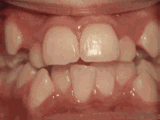

crowding of the teeth

Patient started treatment at age eleven and wore braces for twenty-six months. He loves his new smile.